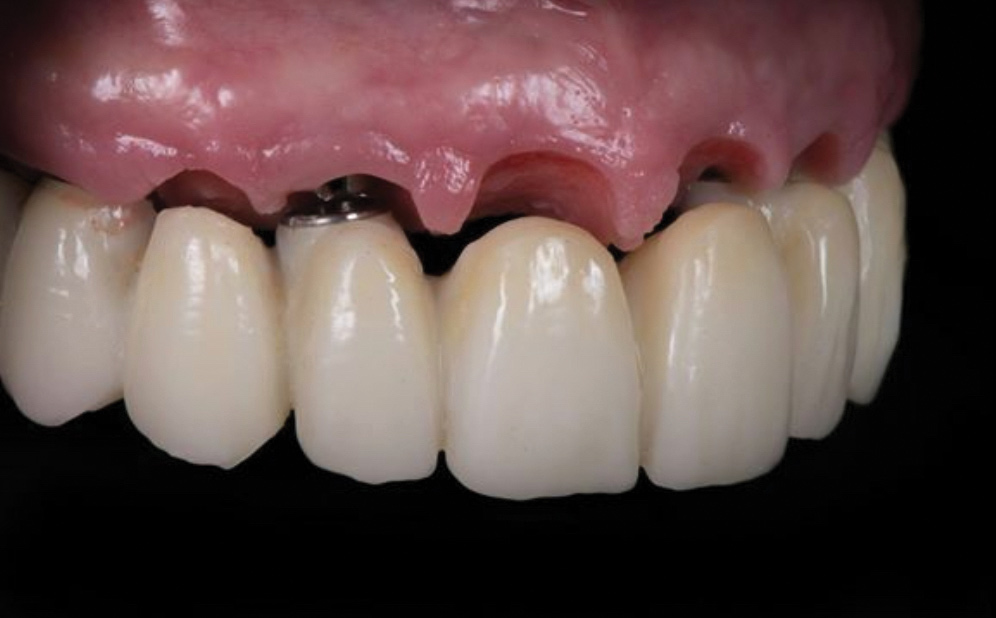

Fig 3. Natural emergence profile of the implant crowns and the pontic in a tooth-only defect prosthesis.

Figure 3